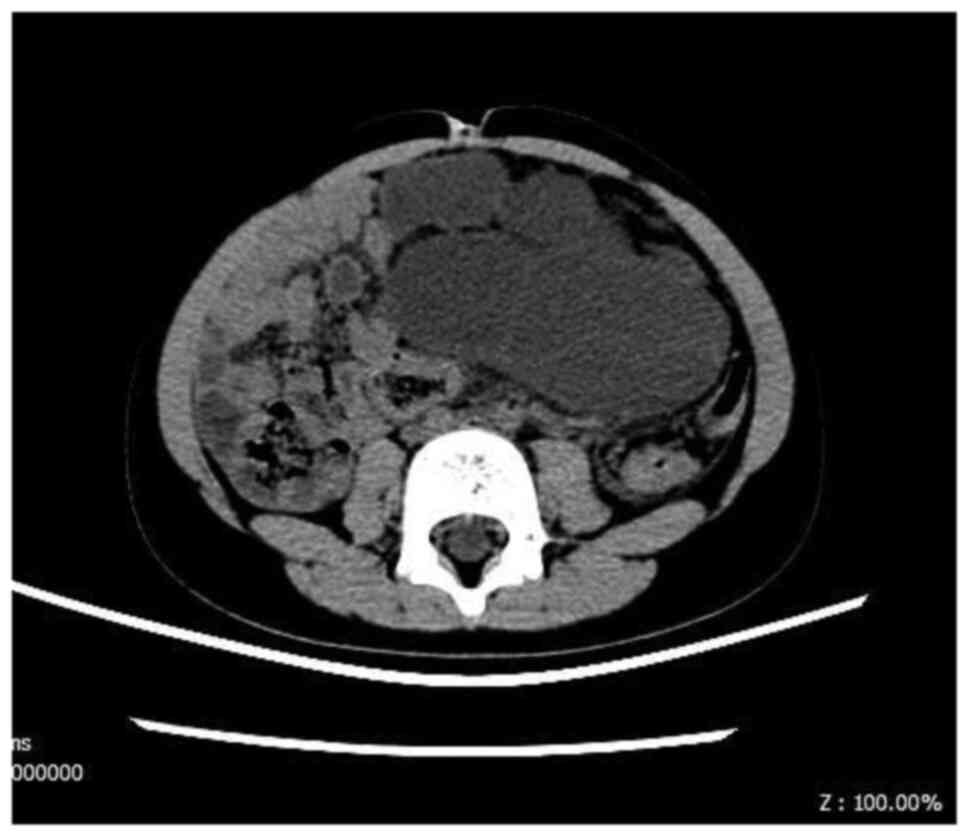

Ultrasound as the first choice was performed in all of the patients to identify the lesion. Computed tomography (Fig. 2) and magnetic resonance imaging were performed for further information in four and five cases, respectively. Overall, 40% (4/10) of the patients were diagnosed with LM preoperatively without any biopsies; three mesenteric cysts, two intra-abdominal cysts and one intestinal duplication were suspected in the remaining six patients preoperatively. By imaging, LM size ranged from 2.8-13.8 cm (mean, 9.5 cm).

Figure 2

Computed tomography imaging of intra-abdominal lymphatic malformation.